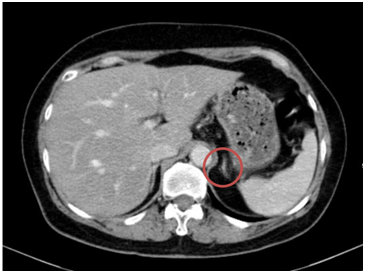

- Chụp cắt lớp vi tính bụng: Theo dõi dày khu trú tuyến thượng thận trái tạo nốt đường kính khoảng 9mm (không thay đổi)

Hình 10. Hình ảnh chụp CT bụng sau điều trị: Nốt tuyến thượng thận trái